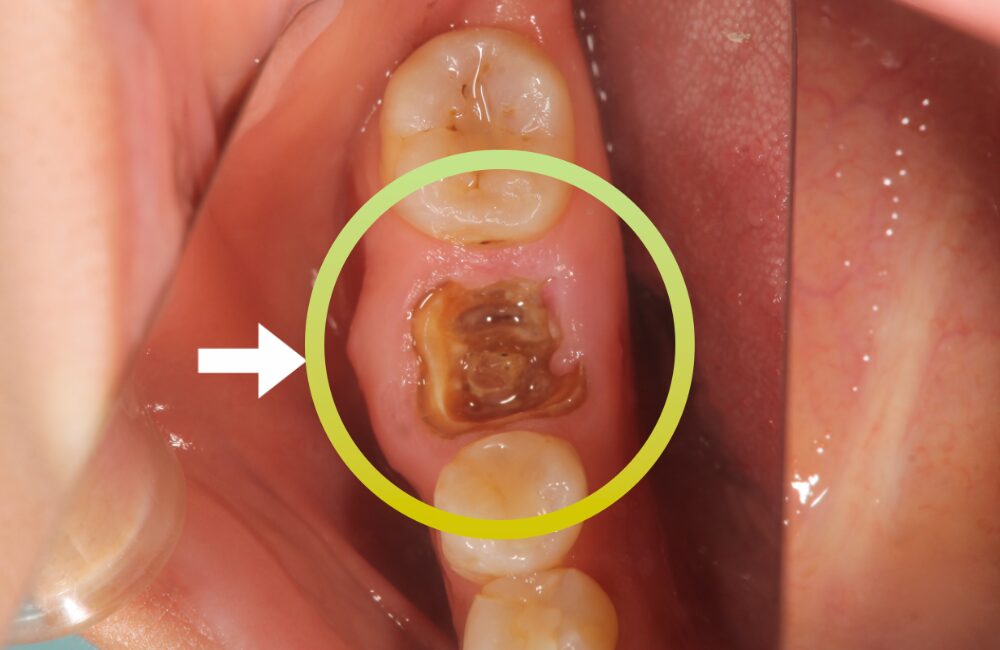

初診時の様子

右下の奥歯が虫歯で抜歯が必要な状態です。